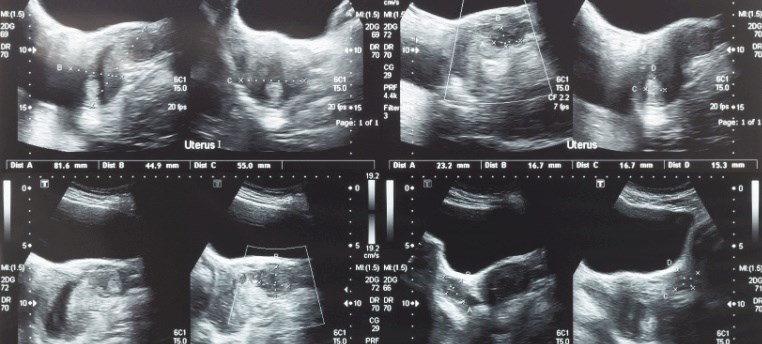

תהליך האבחון של רחם שרירני מתחיל בדרך כלל כאשר אישה פונה לרופא בשל תסמינים כמו דימום וסתי כבד, כאבי אגן, או בעיות פוריות. במקרים רבים, השרירנים מתגלים באקראי במהלך בדיקה גינקולוגית שגרתית. במהלך הבדיקה הגופנית, הרופא ממשש את הבטן התחתונה ומבצע בדיקה וגינלית המאפשרת להעריך את גודל הרחם ולזהות עיוותים או בליטות בצורתו. רחם מוגדל, קשיח למגע או בעל צורה לא סימטרית, מעלה חשד לנוכחות שרירנים. אולטרסאונד הוא אמצעי ההדמיה הראשוני והנפוץ ביותר לאבחון שרירנים. הבדיקה יכולה להתבצע דרך דופן הבטן או בגישה וגינלית, כאשר האחרונה מאפשרת הדמיה מדויקת יותר של הרחם והשחלות. באמצעות האולטרסאונד ניתן לזהות את מספר השרירנים, גודלם, מיקומם והשפעתם על המבנה הכללי של הרחם.

תמונת אולטרסאונד של בטן תחתונה, שחלה ורחם עם גידול או שרירן ברחם של מטופלת. צילום: שאטרסטוק